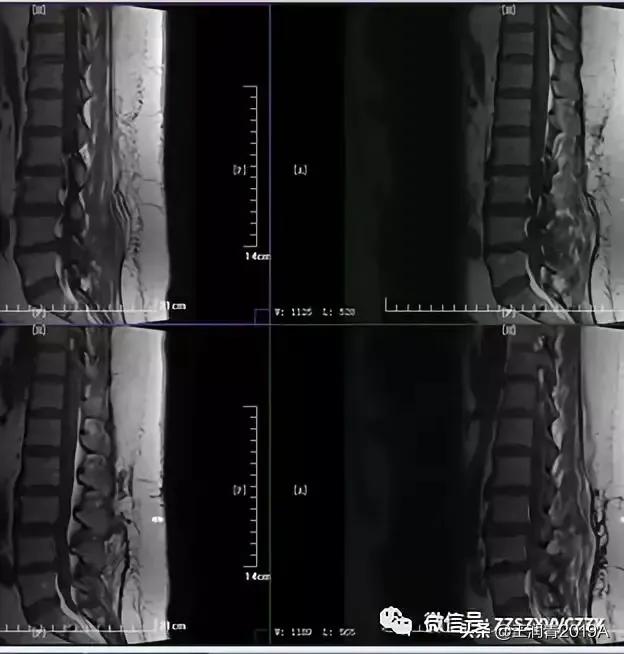

2、腰椎MR增强检查:平腰4椎体层面椎管内异常信号影,考虑腰椎间盘髓核脱出影(腰4-5)(图4-8)